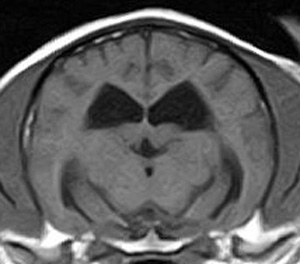

けいれん発作が出るワンちゃんが来院されました。MRI検査では脳に構造上の異常を認めず、特発性てんかんとの診断でお薬での治療となりました。発作は現在のところ、お薬で良好にコントロールされています。